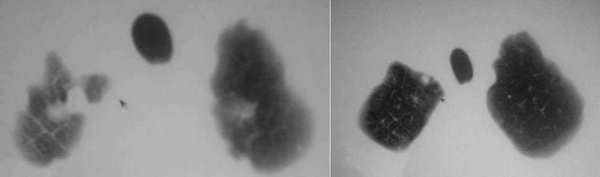

男,53,发热1月余,间断性,用药(不详)既停,停药既烧。有时吐痰、鼻涕带血。

ct所见;两肺胸膜下多发散在大小不一结节状影,部位以右侧为主,多在胸膜下,多数结节内可见不规则空洞,壁厚薄不均,未见液平。